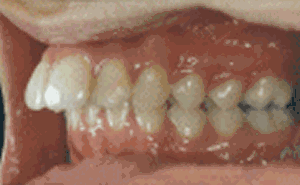

其实“龅牙”是东方人种中较为常见的一类牙颌面畸形,在医学专业上实质是上颌前突畸形或双颌前突畸形,一般不伴有严重的功能障碍,但非常影响美观,患者求治的目的主要是为了改善容貌。寇主任说,现在不用再为自己的龅牙苦恼啦,成人龅牙完全可以通过美容冠进行修复。

龅牙是较为常见的一类牙颌面畸形,龅牙非常影响美观,很多成人朋友希望通过龅牙矫正来改善他们的容貌、牙齿咬合状况,能够拥有灿烂的微笑。但是龅牙美容冠的矫正方法在不同的年龄阶段可以采用不同的方式: